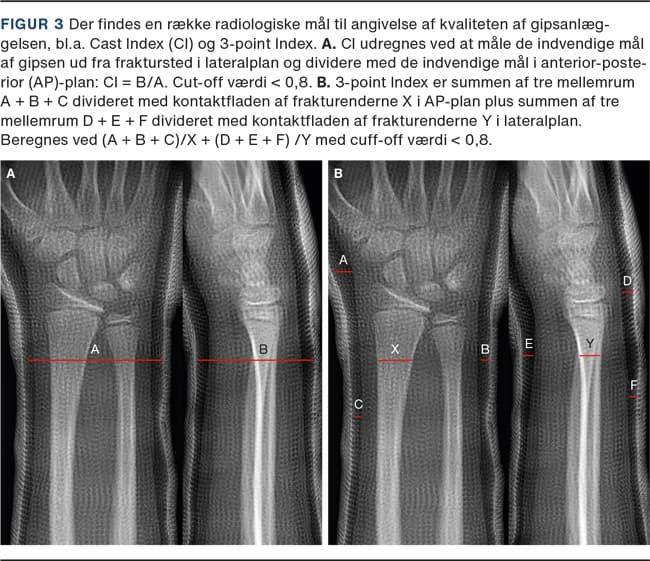

Der er lavet en række radiologiske mål, der angiver kvaliteten af gipsanlæggelsen; 3-pointindex [22], Cast Index (CI) og Gap index [9, 23] (Figur 3). De giver hver især et mål, hvormed man kan forudsige risikoen for frakturskred. Målene kan dog kun benyttes på den cirkulære gips. Ved gipsanlæggelse skal bandagen have et så lavt CI som muligt og anlægges med trepunktsfiksering [5].